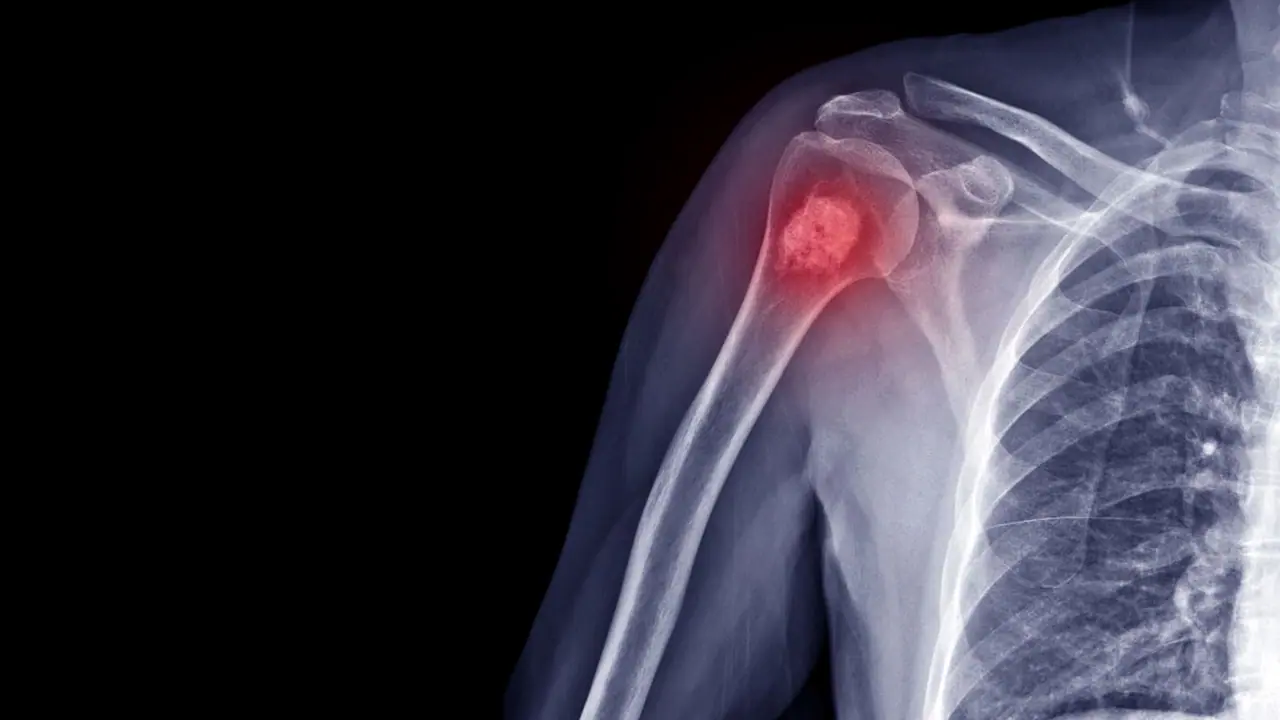

Bone Cancer Detection: उत्तर प्रदेश के आईआईटी के वैज्ञानिकों ने एक बड़ी सफलता हासिल की है। उन्होंने एक ऐसा छोटा और ऑटोमैटिक डिवाइस तैयार किया है, जो हड्डी के कैंसर का शुरुआती स्टेज में ही पता लगा सकता है।

यह खास सेंसर शरीर में मौजूद ऑस्टियोपॉन्टिन नाम के एक बायोमार्कर को पहचानता है जो हड्डी के कैंसर से जुड़ा होता है। यह दुनिया का पहला ऐसा सेंसर है जो इतनी सटीकता से OPN का पता लगा सकता है। इस तकनीक से हड्डी के कैंसर की जल्दी पहचान होने से मरीजों का इलाज सही समय पर शुरू किया जा सकेगा, जिससे जान बचाना आसान होगा।

आईआईटी के डॉ. प्रांजल चंद्रा की टीम ने एक ऐसा सस्ता उपकरण बनाया है, जो बिना किसी केमिकल के काम करता है और हड्डी के कैंसर का पता लगा सकता है। यह उपकरण ग्लूकोज मीटर की तरह काम करता है। यह खास सेंसर सोने और नैनो-मटेरियल से बना है, जिससे यह कम संसाधनों में भी तेज और सटीक जांच कर सकता है। प्रो. चंद्रा ने कहा कि यह तकनीक कैंसर की जल्दी पहचान में मदद करेगी और प्राथमिक स्वास्थ्य केंद्रों को सशक्त बनाएगी। इसका शोध रॉयल सोसाइटी ऑफ केमिस्ट्री के जर्नल नैनोस्केल में प्रकाशित हुआ है।